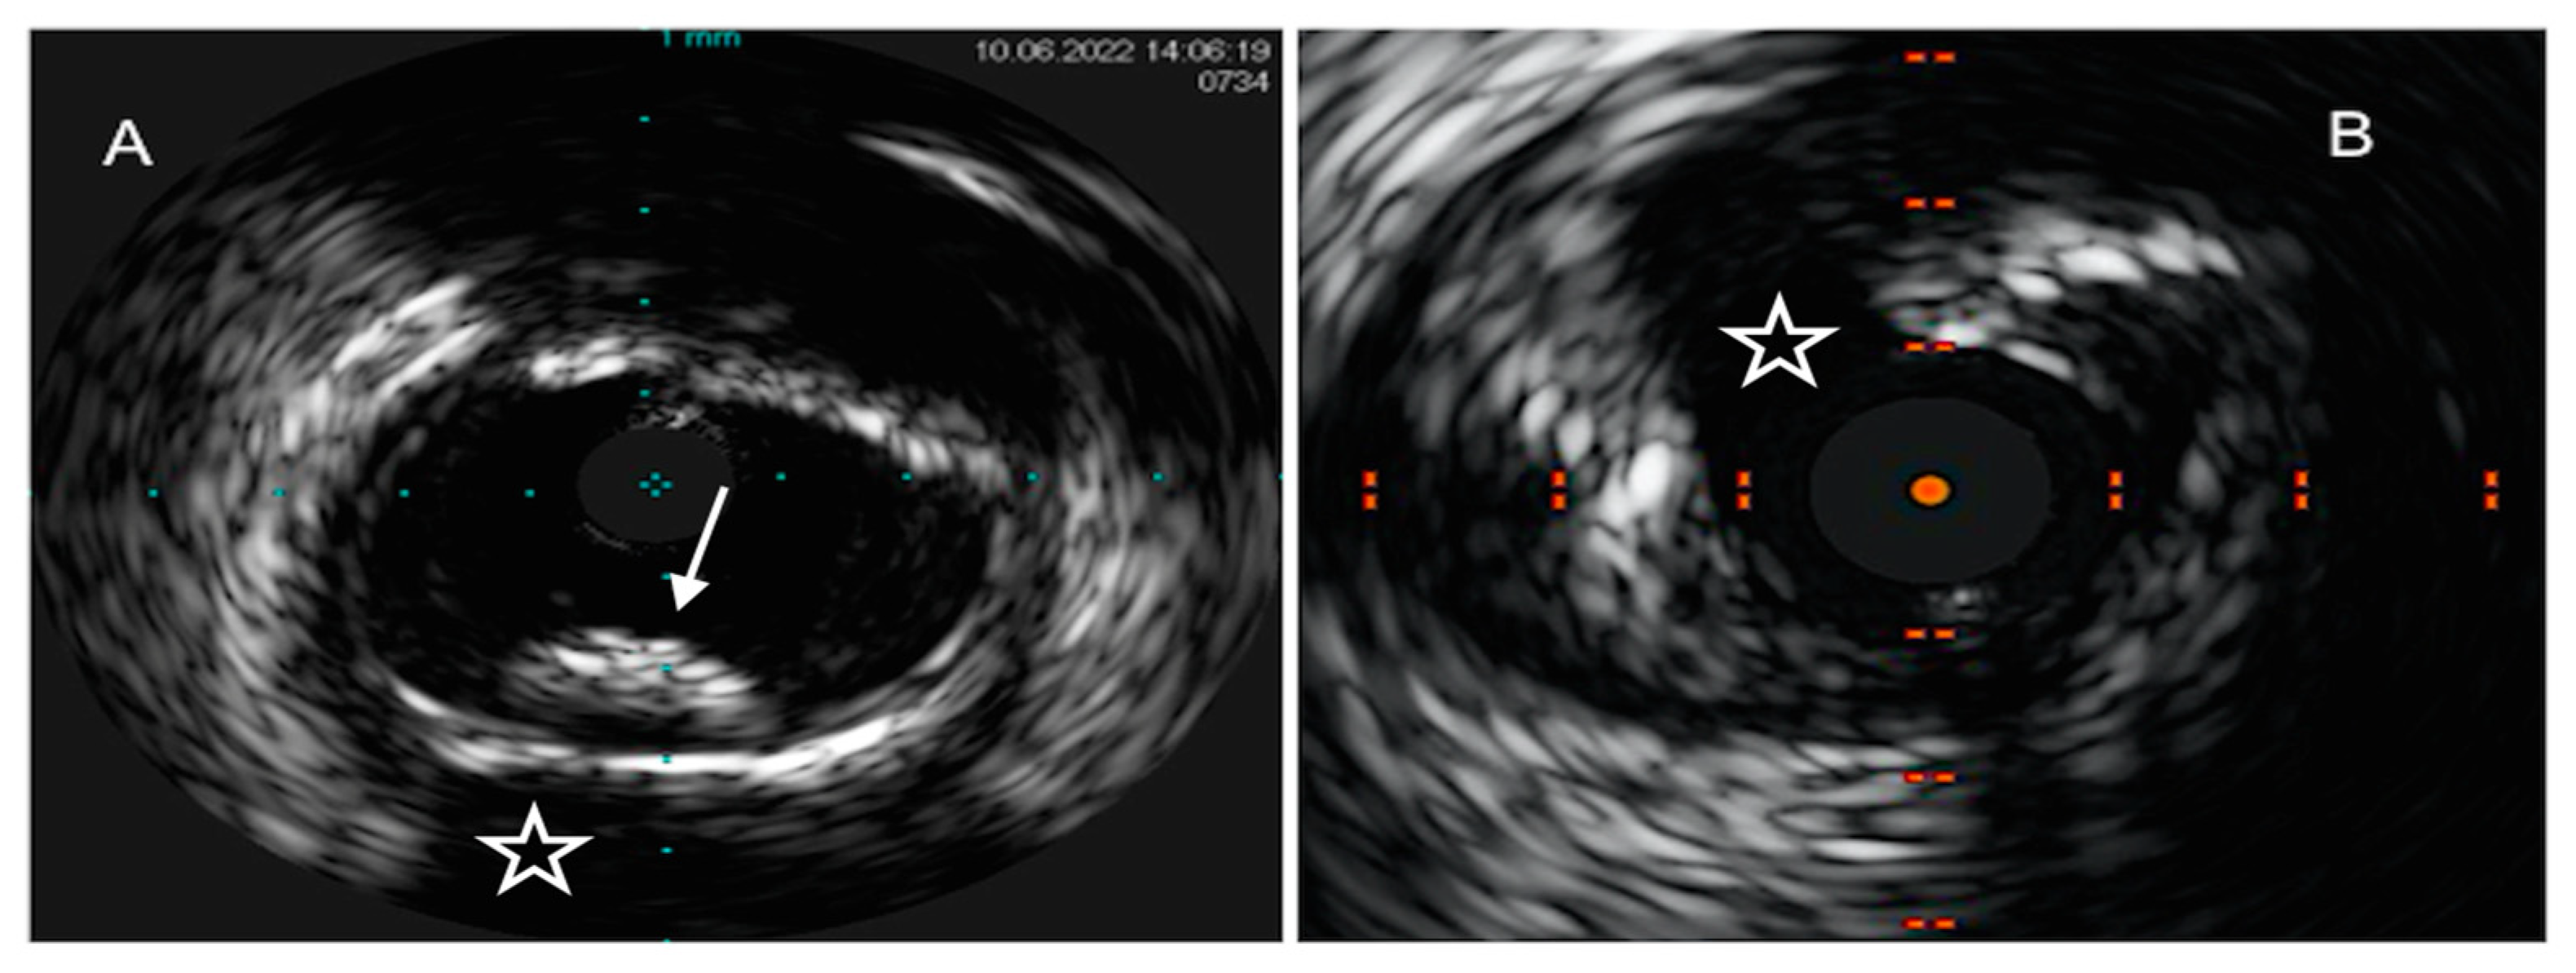

4.1. Intravascular Ultrasound

4.2. Optical Coherence Tomography